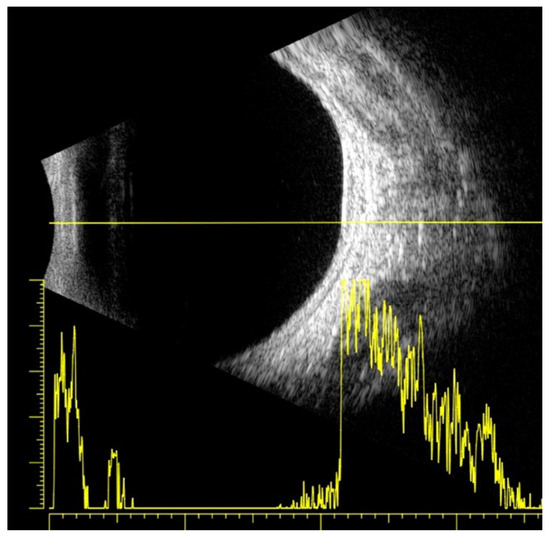

2.3. Diagnostic Assessment